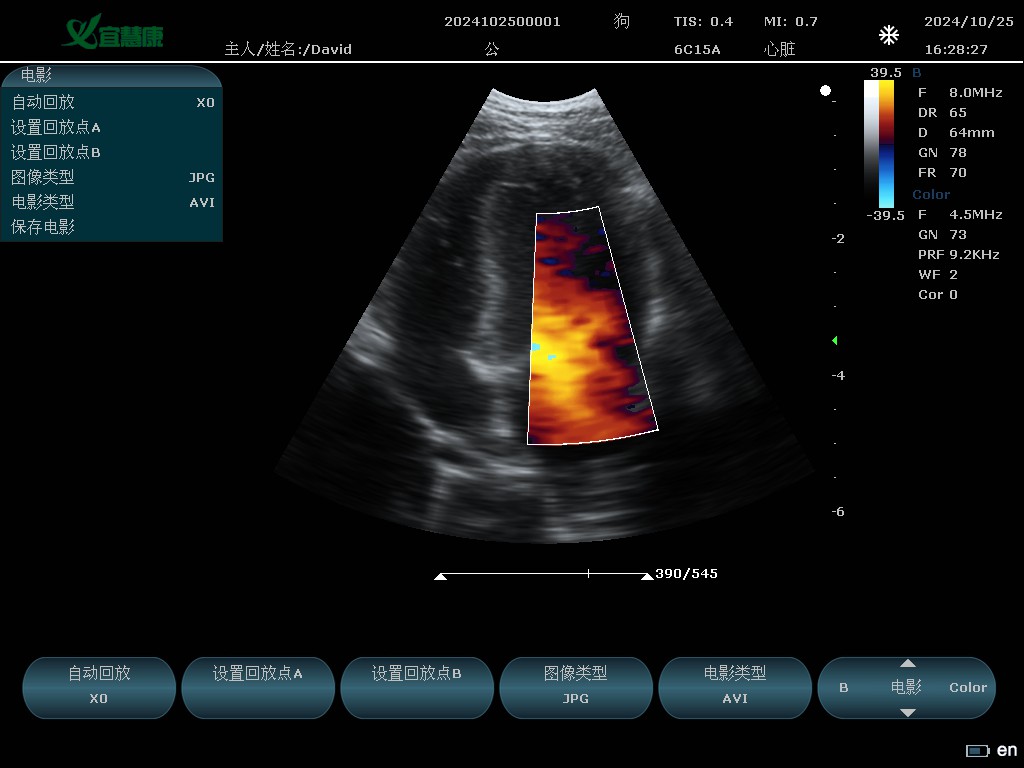

YHK-C90可以用于动物腹部、心脏、产科、小器官、血管、肌腱等方面的检查。支持的动物类型有猫、狗、牛、马、羊 其他。

6C15A: 6.5MHz/R15/80阵元微凸探头;

Color(彩色多谱勒)模式

Color 模式:4.5MHZ、5.0MHZ

Color模式

频率:4.5MHZ、5.0MHZ